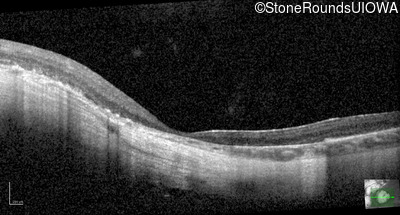

Optical Coherence Tomography - Right - 20/160 -2

Exemplar / OCT Stack

OCT Stack